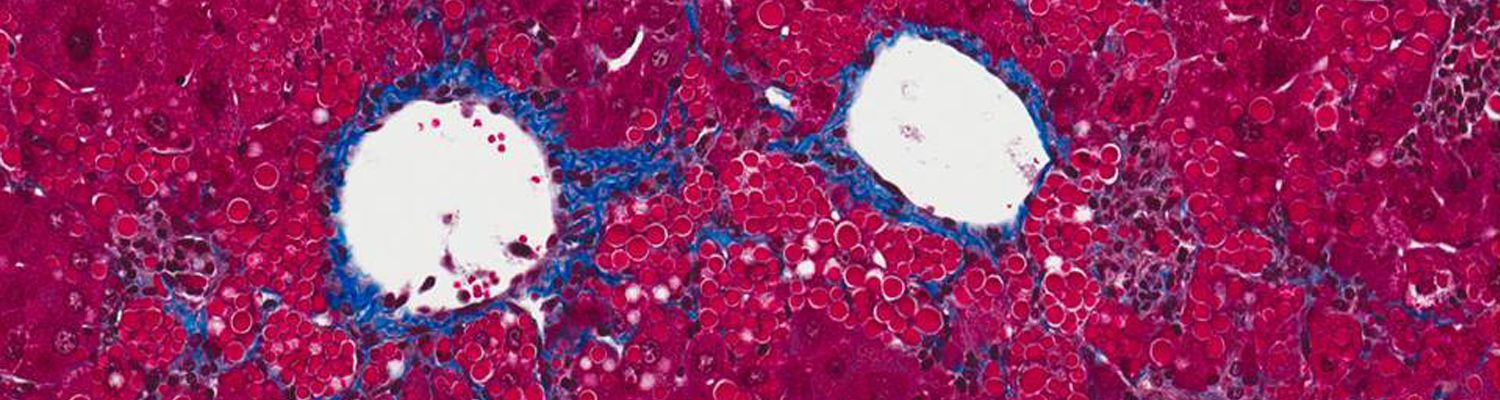

Alpha-one antitrypsin deficiency has been the focus of our lab since its inception. Building up on the work of Dr Terry Flotte directed towards production of the normal AAT protein (see the results of our clinical trial here), we developed a dual function vector that not only allows production of the normal AAT but also silences the mutated, toxic Z-AAT protein.